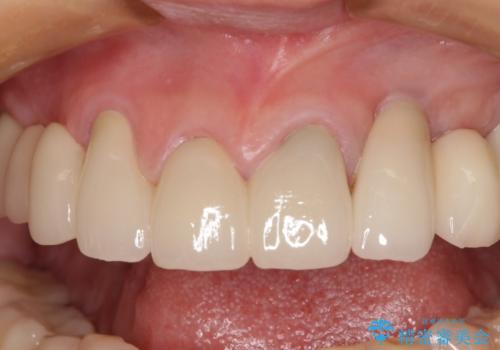

上顎はほぼ全ての歯をセラミッククラウンにて補綴治療を行う必要があるため、気になるデコボコや深い咬み合わせを改善するために下顎と上顎の臼歯部の矯正治療を行うこととしました。

過蓋咬合(下顎前歯が隠れてしまうほどの深い咬み合わせ)のため、スムーズに歯が動かず矯正治療に時間がかかりましたが、無事に仕上げることができました。